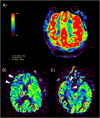

Methods: Patients with biologically-confirmed COVID-19 and neurological manifestations undergoing a brain MRI with technically adequate arterial spin labeling (ASL) perfusion were included in this retrospective multicenter study. ASL maps were jointly reviewed by two readers blinded to clinical data. They assessed abnormal perfusion in four regions of interest in each brain hemisphere: frontal lobe, parietal lobe, posterior temporal lobe, and temporal pole extended to the amygdalo-hippocampal complex.

Results: Fifty-nine patients (44 men (75%), mean age 61.2 years) were included. Most patients had a severe COVID-19, 57 (97%) needed oxygen therapy and 43 (73%) were hospitalized in intensive care unit at the time of MRI. Morphological brain MRI was abnormal in 44 (75%) patients. ASL perfusion was abnormal in 53 (90%) patients, and particularly in all patients with normal morphological MRI. Hypoperfusion occurred in 48 (81%) patients, mostly in temporal poles (52 (44%)) and frontal lobes (40 (34%)). Hyperperfusion occurred in 9 (15%) patients and was closely associated with post-contrast FLAIR leptomeningeal enhancement (100% [66.4%-100%] of hyperperfusion with enhancement versus 28.6% [16.6%-43.2%] without, p = 0.002). Studied clinical parameters (especially sedation) and other morphological MRI anomalies had no significant impact on perfusion anomalies.

Conclusion: Brain ASL perfusion showed hypoperfusion in more than 80% of patients with severe COVID-19, with or without visible lesion on conventional MRI abnormalities.